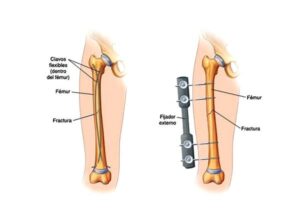

El objetivo del tratamiento de las fracturas es permitir que el hueso sane y se fusione de nuevo. A menudo, esto puede lograrse inmovilizando el hueso durante varios meses con la ayuda de una escayola y una férula. Cuanto más grave es la fractura, más probable es que se recomiende la cirugía.

Por ejemplo, una fractura abierta o conminuta requerirá una intervención quirúrgica para garantizar que el hueso vuelva a crecer por completo y soporte su peso con seguridad. La reparación quirúrgica implica el uso de varillas, tornillos o placas metálicas para fijar el hueso en su sitio o alinearlo mientras se cura.